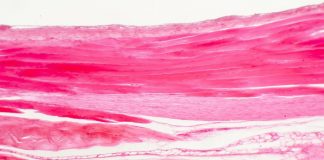

Zespół Marfana to choroba o podłożu genetycznym. Dotyczy ona tkanki łącznej i objawia się w bardzo charakterystyczny sposób. Osoba dotknięta tym schorzeniem boryka się...